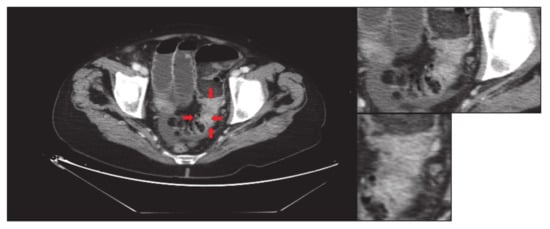

- First, an image of tumour is saved without limitation in original size as “large-original.tiff” (i.e., Figure 1). The sequence of obtaining the images is very important to speed up the process and ensure that the images have the same focus when they are enlarged. An expert radiologist searches the cut with the largest diameter of the tumour. All images must be saved in “.tiff” format, as we will explain later.